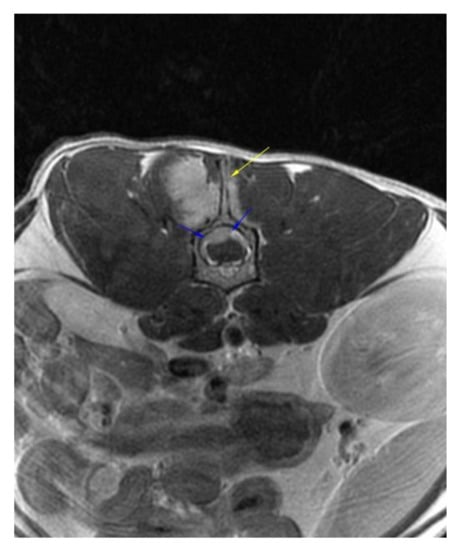

Successful Treatment of Vertebral Osteosarcoma in a Cat Using Marginal Surgical Excision and Chemotherapy

:1. Case Description

2. Materials and Methods

3. Results